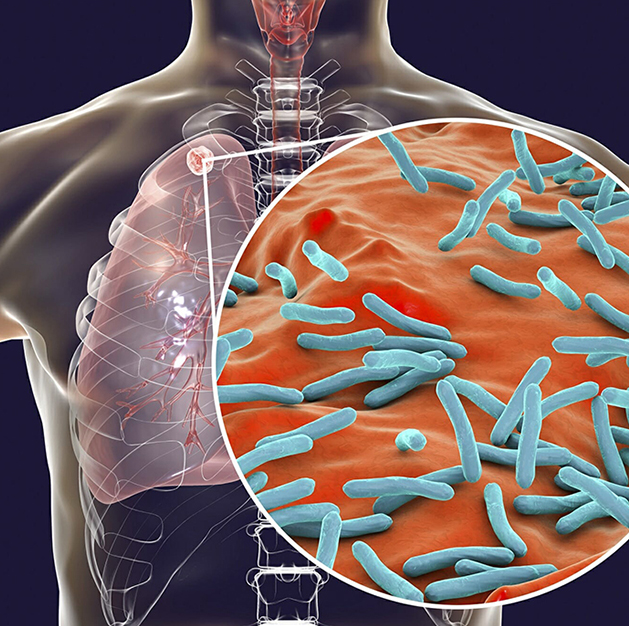

Tuberculosis (TB)